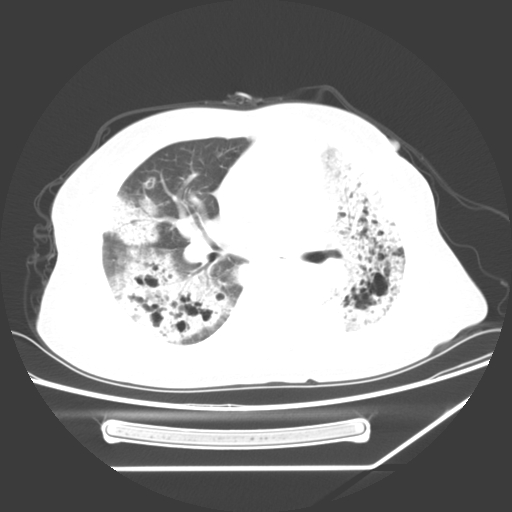

标题: CT25393:病人45岁,咳嗽,吐黄痰带血丝,发热,胸闷月余 [打印本页]

标题: CT25393:病人45岁,咳嗽,吐黄痰带血丝,发热,胸闷月余

1、左肺中央型肺癌并双肺弥漫性转移   2、双肺部感染    3、肺大泡     4、左侧胸腔积液

双侧肺弥漫性病变,可见“空泡征”及“蜂窝征”,考虑肺泡癌可能性大,左侧胸腔积液,考虑胸膜受累可能!

1)不排除肺泡癌可能。2)左侧胸腔积液。